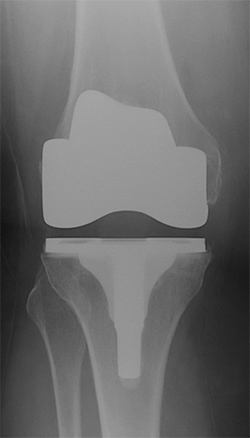

The knee joint is made up of the femur (thigh bone) sitting on the tibia (shin bone) with the patella (knee cap) running along a groove in the front of the femur. Arthritis can affect any or all of these parts of the joint. In arthritis, the joint surface cartilage which covers the ends of the bones, is damaged or worn out. When the worn out surfaces rub against each other, they cause pain. In a total knee replacement, the worn out cartilage surfaces are replaced with metal surfaces which are impacted or cemented into the bone; a hard plastic liner sits between the metal surfaces so that they move smoothly.

A total knee replacement is performed under an anaesthetic (either a general or spinal anaesthetic). An incision is made in the front of the knee and the knee joint is opened up. The ends of the femur and tibia are reshaped and the metal replacements are inserted onto the bones. A plastic liner is then locked onto the metal component of the tibia. If the patella is also very worn out, the undersurface of the patella is smoothed off and a plastic button is cemented in to replace the removed bone.

Research has shown that the results of a total knee replacement depend on the position that the prostheses are placed in. The surgeons at Melbourne Hip and Knee use the most current techniques to achieve the best position for the prostheses in your knee.